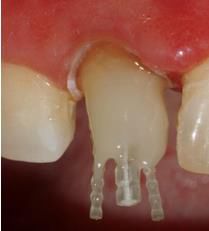

在操作的過程中要注意無菌操作,保證纖維樁的無菌狀態(tài)。推薦將樹脂核堆好之后再截斷纖維樁,而不是截斷后再粘接。如下圖: